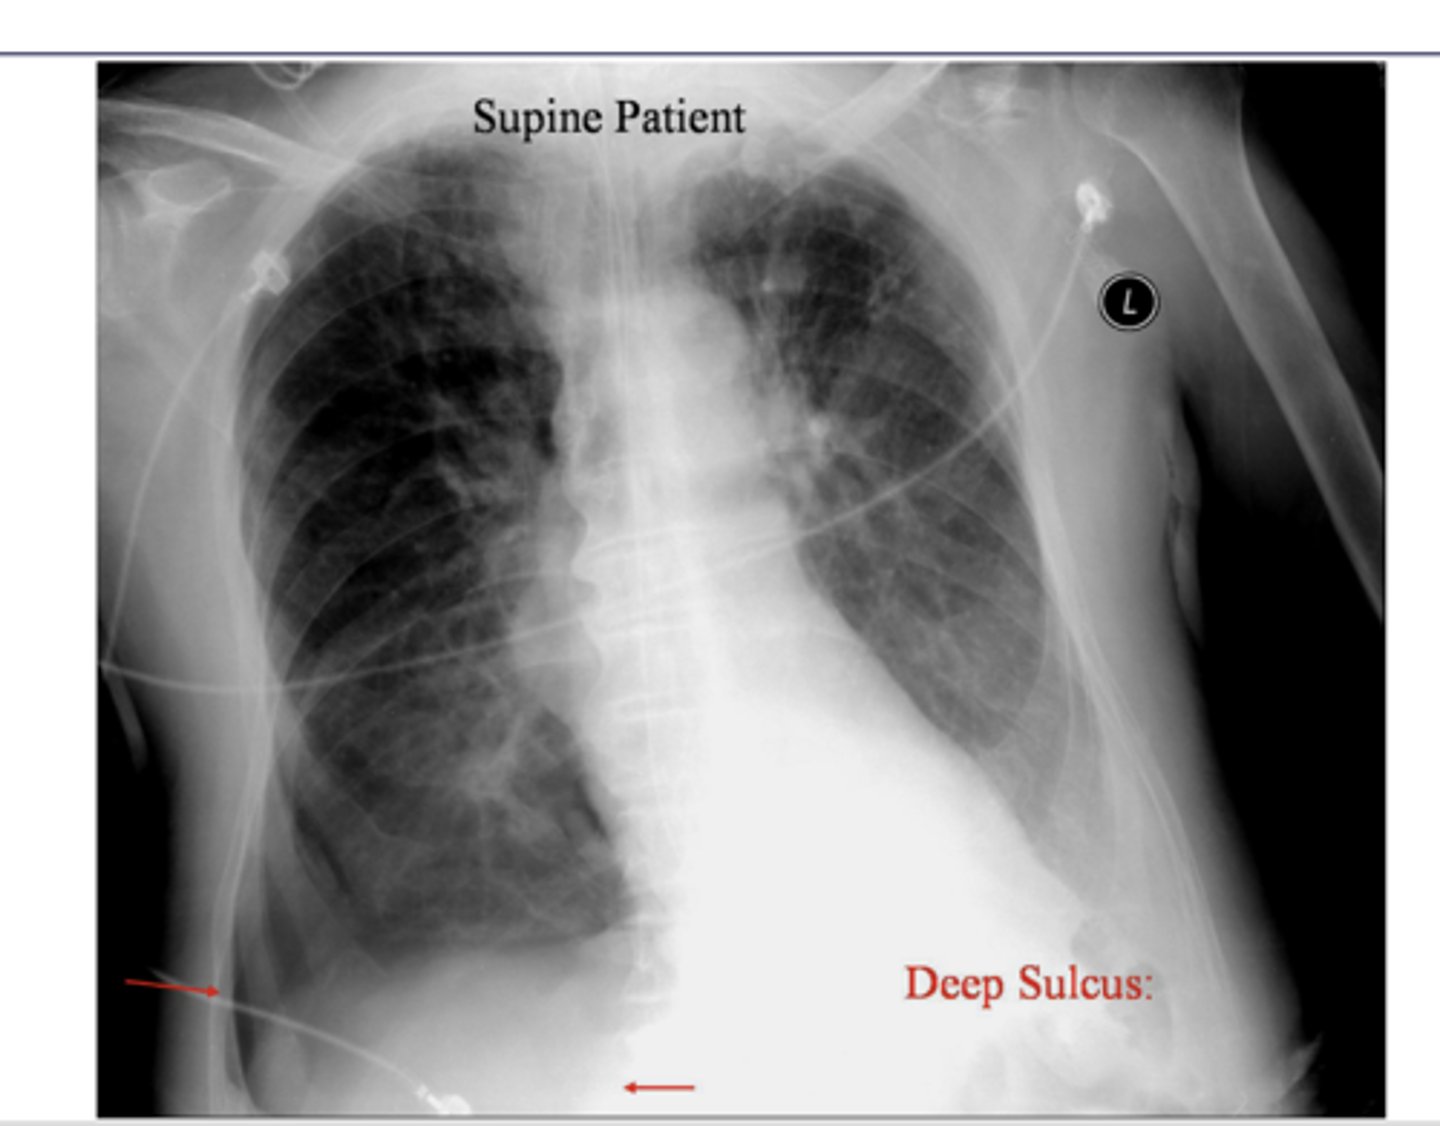

When pt supine, xray findings support pneumothorax

It represents lucency of the lateral costophrenic angle extending toward the hypochondrium

What sign is this?

<p>What sign is this?</p>